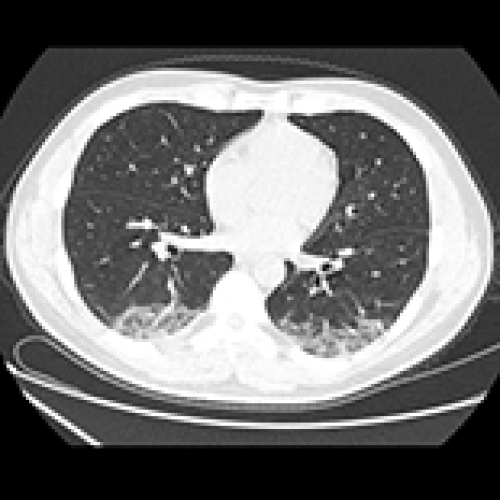

06 Oct 2021 : Database Analysis

A Simple Clinical Prediction Tool for COVID-19 in Primary Care with Epidemiology: Temperature-Leukocytes-CT Results

Wanming Hao, Long Zhao, Xinjuan Yu, Song Wu, Weifeng Xie, Ning Wang, Weihong Lv, Akshay Sood, Shuguang Leng, Yongchun Li, Qing Sun, Jun Guan, Wei Han

DOI: 10.12659/MSM.931467

Med Sci Monit 2021; 27:e931467

3,023 988 0

3023 988 0